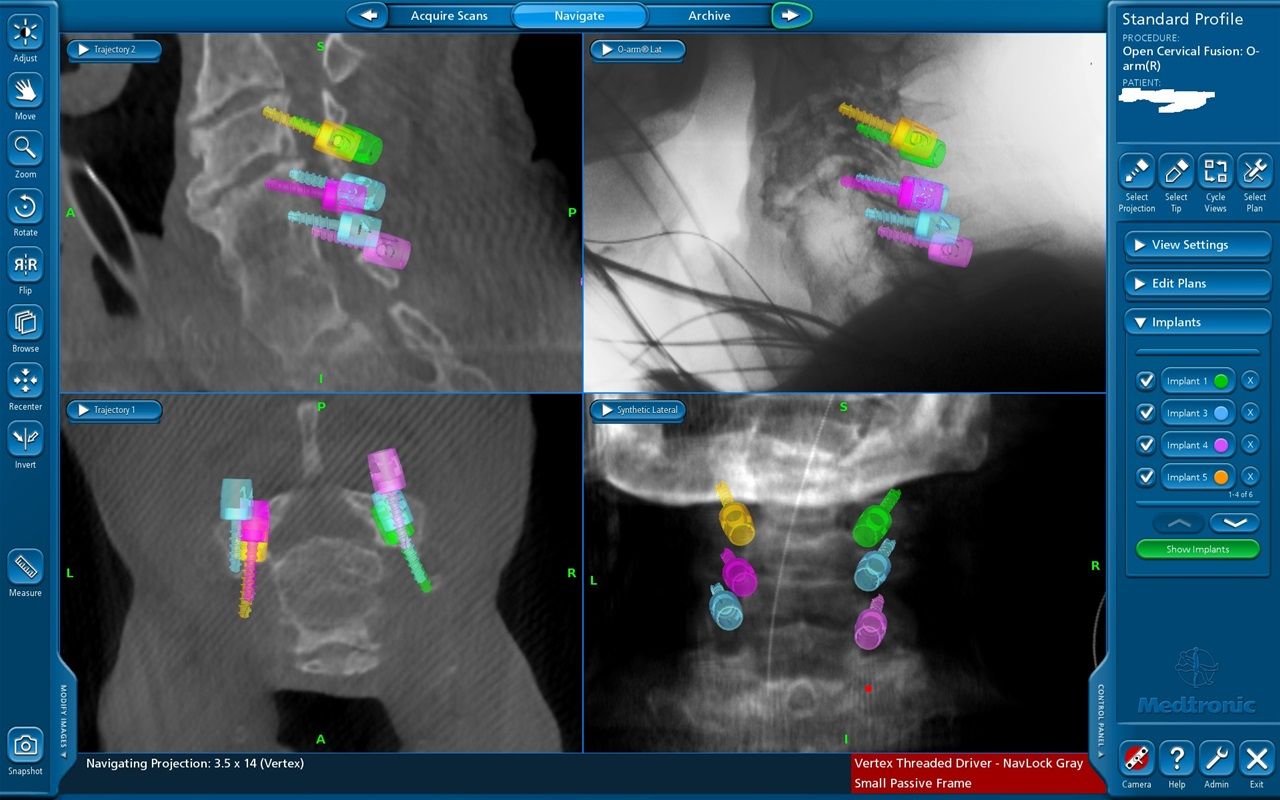

Νευροπλοήγηση με Stealth Station και διεγχειρητική απεικόνιση με 0 ARM.

Διεγχειρητική απεικόνιση οπίσθιας σπονδυλοδεσίας ΑΜΣΣ με O ARM